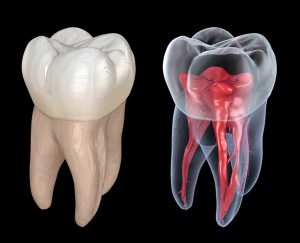

Micro-CT

Micro-CT, or micro-Computed Tomography, is an imaging system that provides high-resolution 3D images of biological structures. This system uses X-rays to create cross-sectional images of the body, which are then reconstructed into a 3D image. Micro-CT has applications in the study of anatomical structures, bone density, and tissue engineering. For example, micro-CT can be used to study bone structure and density, to analyze the microarchitecture of tissues, and to study the growth of tumors.